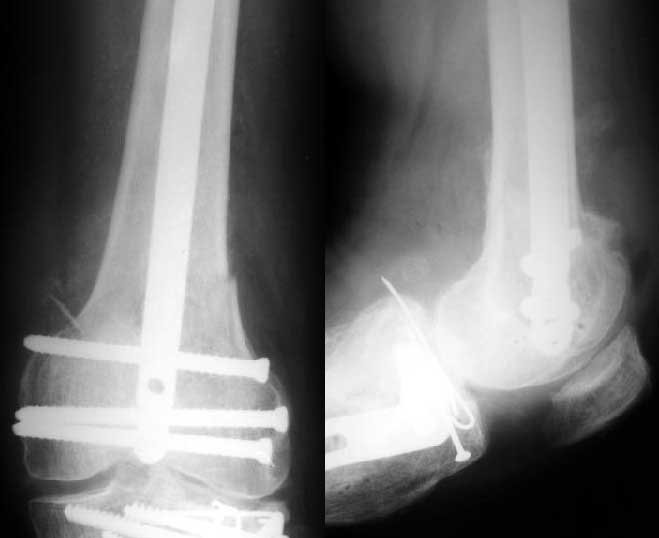

S> Трудно представить , как удастся закрепить дистальный отломок гвоздем

Винтами. Снимок в приложении.